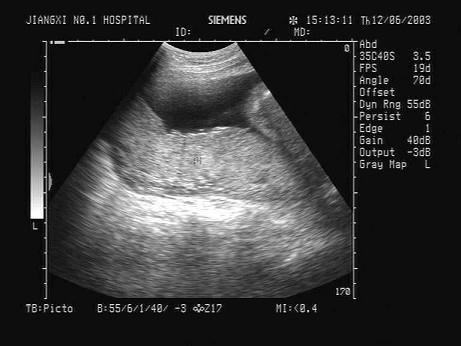

根据超声声像图,提示结构为?(?)A.脐带B.胎盘C.胎儿躯干D.胎儿臀部E.子宫肌层

问题 根据超声声像图,提示结构为?(?)

选项 A.脐带 B.胎盘 C.胎儿躯干 D.胎儿臀部 E.子宫肌层

答案 B